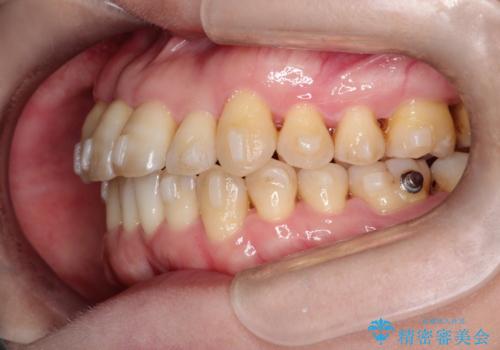

【インビザライン】ずれた前歯の噛み合わせをなおしたい

- 前歯の噛み合わせが悪いことを主訴に来院されました。

歯周病も併発していたため、歯牙への負担が少なくなるように治療計画をたて、インビザラインにて治療を完了しました。

矯正開始前に半年間、歯周治療を行ってからインビザラインを装着しています。